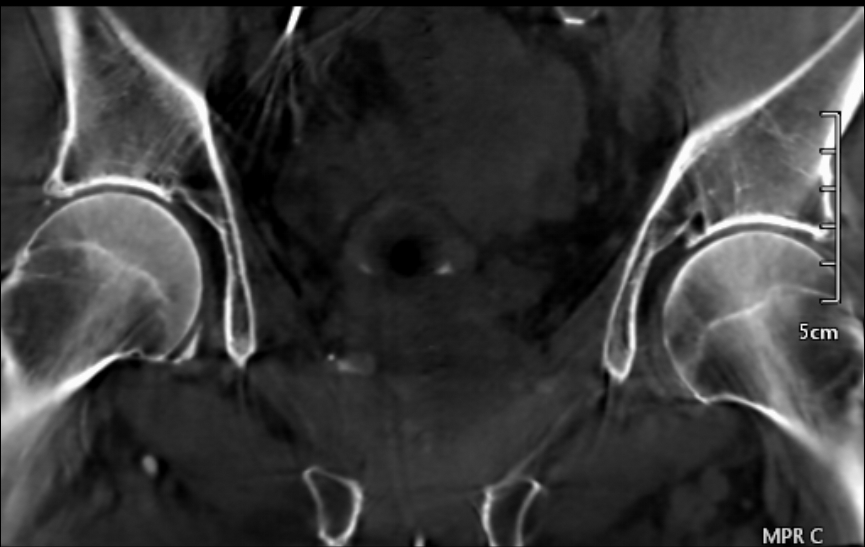

Just curious if anyone has Canon Alphenix systems with CBCT options. Our new system has this subtle central ring artifact, even after detector replacement. It appears stronger with a uniform ACR phantom, but is also visible from clinical cases, especially from sagittal or coronal views.

[cid:ab3ad1a8-4df5-4835-b692-ad3a79ecdb9c]